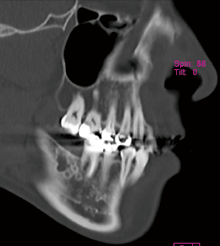

図❷ 初診時のCT画像(矢状断)

画像所見:パノラマX線写真では、欠損した7部骨内に、多房性、泡沫状の透過像を認め、6の遠心根は吸収していた(図❶)。CT画像では同部に細かい泡沫状の隔壁を有しており、内部に石灰化像はなかった。境界は比較的明瞭で、周囲への浸潤は認めなかった。また、下歯槽神経には近接していなかった(図❷)。